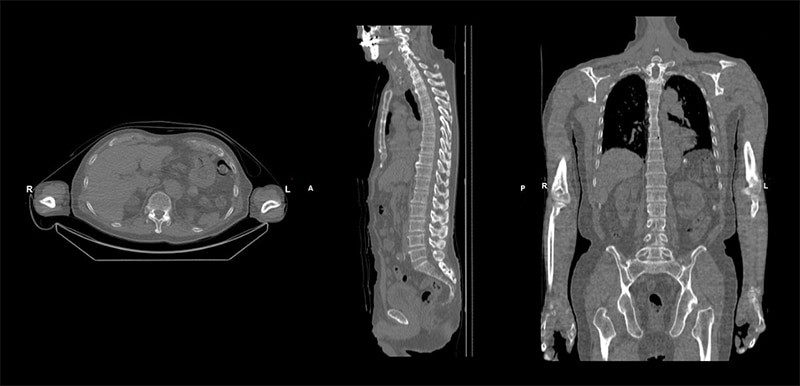

骨シンチグラフィでは全例でSPECT/CT撮影を行っています。吸収補正用CTであるため最大管電流が30mAと聞いており、当初はFusion用のCT画像としての画質に不安もありましたが、期待を超える十分な画質が得られています。また、Smart Consoleを利用することで、骨シンチグラフィで収集するWhole Body画像をCT装置のスカウト画像のように使用してSPECT/CTの収集範囲を設定することができ、非常に操作もしやすいと感じています。また、Fusion画像作成も解析用ワークステーションXelerisでAxial、Sagittal、Coronalを簡単に作成することができるため、日々有用な画像を読影医に提供することが出来ています。

30mAのCT画像

骨SPECT/CT Fusion画像